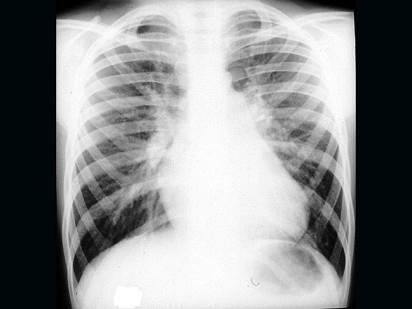

问题 先天性心脏病患儿胸部X线透视下可见“肺门舞蹈”征,心影呈梨形,如图,最可能的诊断为 ( )

选项 A、大动脉转位 B、主动脉缩窄 C、肺动脉瓣狭窄 D、房间隔缺损 E、法洛四联症

答案 D